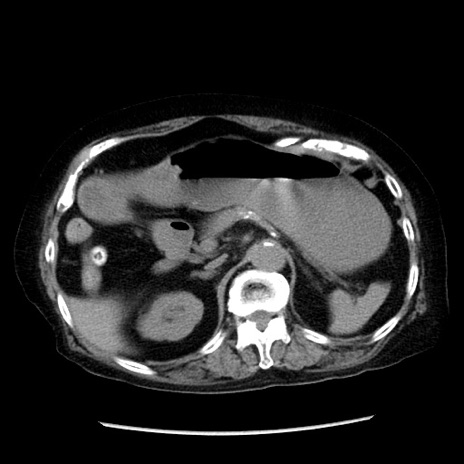

冠状断像